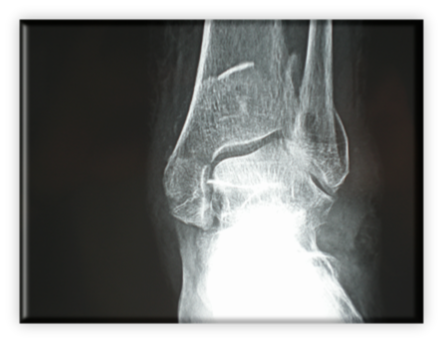

Ποδοκνημική - Άκρος πόδας ΤΡΙΣΦΥΡΙΟ ΚΑΤΑΓΜΑ ΠΟΔΟΚΝΗΜΙΚΗΣ

Πρόκειται για αρκετά σοβαρό τραυματισμό, αφού το κάταγμα επεκτείνεται στην άρθρωση (ενδαρθρικό) με συνέπεια αυξημένα ποσοστά μετατραυματικής αρθρίτιδας της ποδοκνημικής. Αυτό καθιστά την ακριβή ανάταξη της αρθρικής επιφάνειας επιβεβλημένη. Ειδικότερα, αν το κάταγμα οπισθίου σφυρού περιλαμβάνει το 1/3 ή περισσότερο της αρθρικής επιφάνειας πρέπει να αναταχθεί και οστεοσυνθεθεί. Τα συνυπάρχοντα κατάγματα του κάτω πέρατος της περόνης (έξω σφυρό) και κάτω έσω πέρας της κνήμης (έσω σφυρό) καθιστούν την άρθρωση  εξαιρετικά ασταθή. Η όλη κατάσταση μπορεί να παρομοιαστεί με ένα τρίποδα του οποίου έχουν σπάσει και τα τρία πόδια. Φτιάχνοντας το ένα ή τα δύο μόνο πόδια, δεν μπορεί να έχει ισορροπία ο τρίποδας, οπότε πέφτει. Αντίστοιχα είναι τα πράγματα και για την άρθρωση της ποδοκνημικής που είναι μια στηρικτική άρθρωση.

Η θεραπεία είναι χειρουργική.